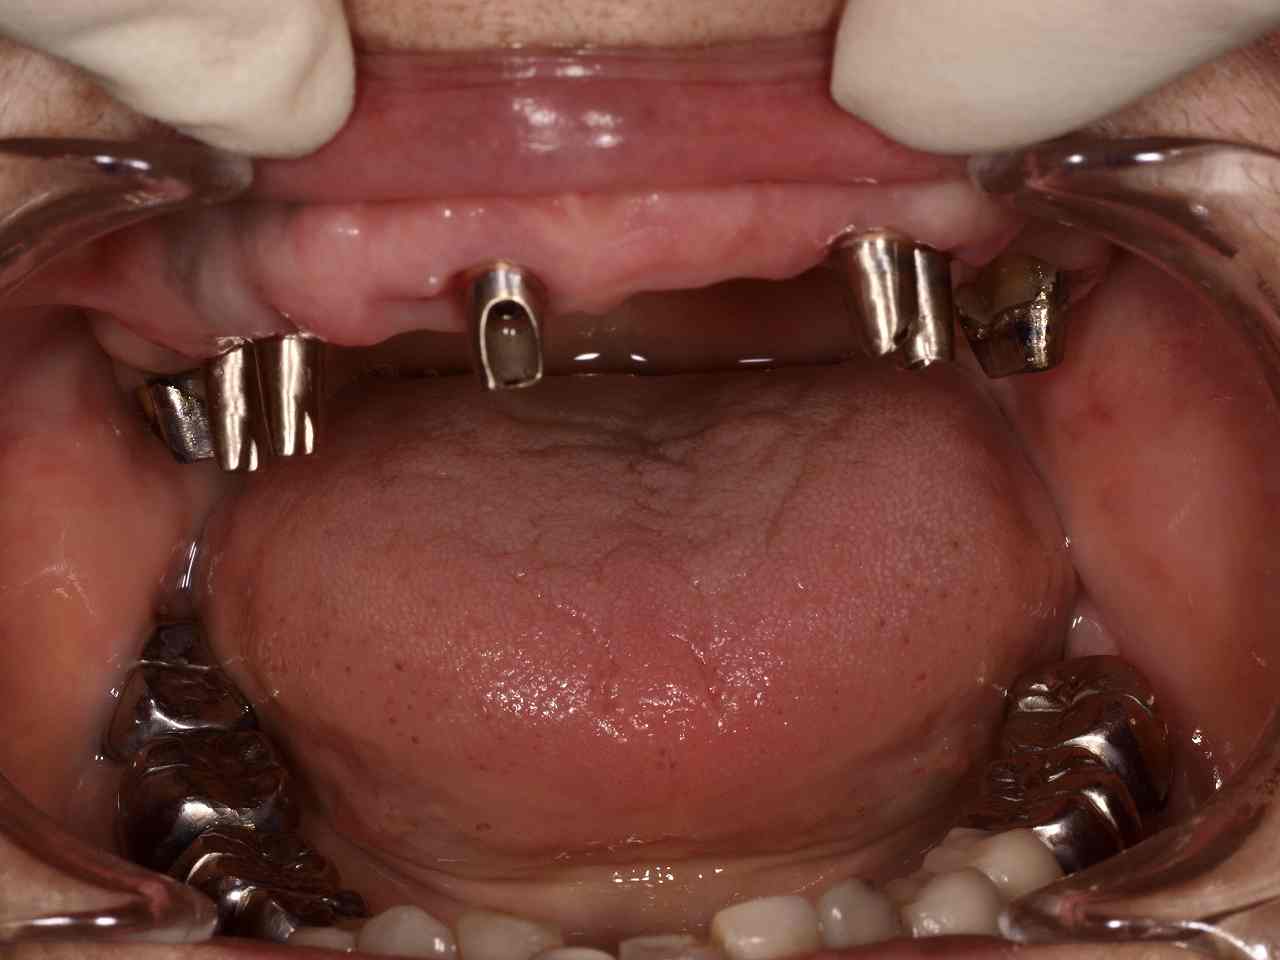

ブログ一覧|広島市安佐南区の歯科医院 ブログ一覧 トップ ブログ一覧 お知らせ スタッフブログ ブログ一覧 2018/04/24 口腔内にて合せたところです。 しっかりした補綴を作っていきます。 2018/04/24 メタルボンドにて作成。 2018/04/24 インプラントブリッジ 2018/04/24 口腔内にてシェード合せを行っています。 この操作が仕上がりの明暗を分けます。 2018/04/24 ジルコニアクラウンの作成 シンタリングからステインまで 2018/04/24 インプラント周囲炎 2018/04/24 歯牙の牽引 2018/04/23 歯牙破折。 牽引にて保存治療へ。 << 1 2 3 4 5 … 660 661 662 663 664 … 870 871 872 873 874 >> Web診療予約 初めての方へ 選ばれ続ける理由 院内設備について 歯が痛いしみる一般歯科 歯がぐらぐらする歯周病 健康な歯を保ちたい予防歯科 子供の虫歯予防をしたい小児歯科 銀歯をセラミックに審美歯科 白い歯を目指しませんか?ホワイトニング 矯正専門医がいるので安心矯正歯科 抜けた歯を補いたいインプラント・入れ歯 医院案内 スタッフ紹介 メリィハウス歯科クリニックオフィシャルホームページ ラベンダー歯科クリニックオフィシャルホームページ お知らせ・ブログ ホーム 診療科目 一般歯科 歯周病治療 予防治療 小児歯科 審美治療 ホワイトニング 矯正歯科 入れ歯・インプラント マウスピース矯正 初めての方へ 院長・スタッフ 設備紹介 医院案内・アクセス メニューを閉じる